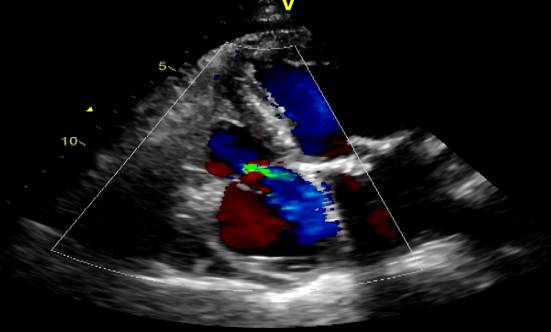

心超(2013-02-01)LA 5.3 RA 4.6 RV 2.7 LV 5.6 LVEF 0.60 TR 3.4(PG=45mmHg)二尖瓣前叶脱垂伴中-重度关闭不全 左心房、右心房、左心室扩大 主动脉瓣钙伴轻中度关闭不全 三尖瓣中度关闭不全 肺动脉高压。

\u000b心超(2015-09-22):二尖瓣前叶脱垂伴中度关闭不全、主动脉瓣钙化,LA(5.4)、RA(4.2)、LV(6.4)、 LVEF 0.40,三尖瓣中度、主动脉瓣中度返流、肺动脉高压(PG=36mmHg)、心功能减低 。